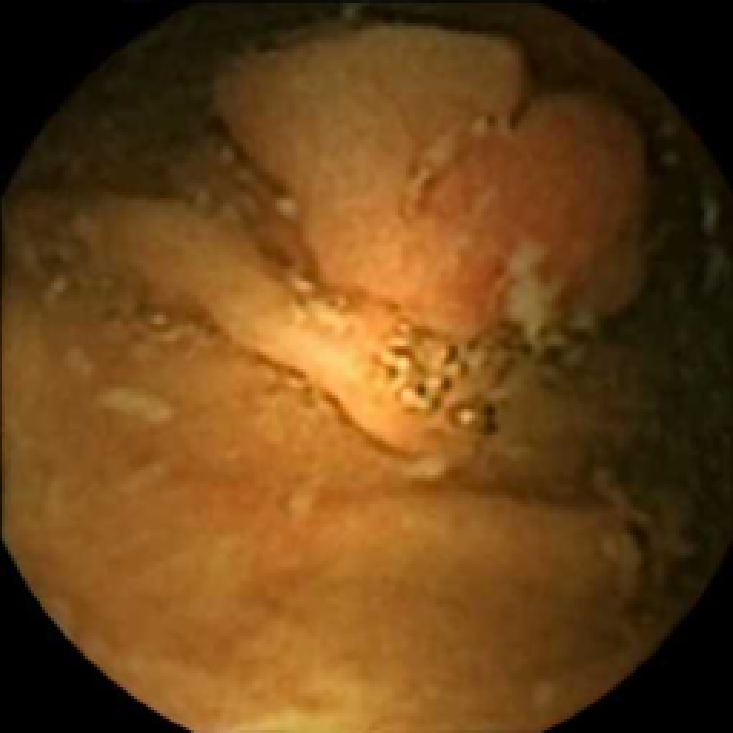

In Figure 5 we show the circles of radius corresponding to the features that were correctly classified as polyps by (29). We observe that the classifier was able to identify the polyps of a variety of shapes even in the presence of small amounts of trash liquid (first row) or when the polyps are located next to mucosal folds (rows two to four in column (c)).

The examples of incorrect classification of frames are presented in Figure 6. The first two examples show false negatives, each highlighting a possible source of classification error. The example in column (a) shows the case where the feature corresponding to the polyp was too stretched out and thus was rejected by the eccentricity criterion (21). In contrast, the feature corresponding to the polyp in column (b) has passed the combined geometric criterion (22), but the radius was below the threshold of the binary classifier. Examples in columns (c) and (d) show the two sources of possible false positives. The false positive detection in column (c) is due to insufficient illumination correction. The bright spot is not fully corrected at the pre-processing stage and subsequently generates a polyp-like feature in the mid-pass filtered frame that happens to pass through all the criteria. Finally, in column (d) a mucosal fold is classified as polyp. Note that such cases are the most difficult to deal with, as the mucosal folds can often be hard to distinguish from polyps even for a human operator.